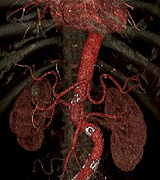

当院では下記の計測も行っております。お気軽にお声掛け下さい。

内脂肪測定

Fat Pointer

腹部CTを撮影したデーターより内臓脂肪値の計測ができます。

患者様に対してもわかりやすく色分けすることで、生活習慣病の診断に有用です。